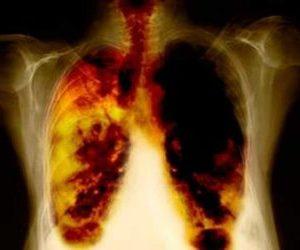

Гнойный плеврит — воспалительное заболевание, характеризующееся накоплением гнойного экссудата в плевральной полости. Это состояние может привести к серьезным осложнениям и угрожать жизни пациента. В статье рассмотрим симптомы гнойного плеврита и основные принципы лечения, включая показания к антибиотикам. Знание этих аспектов поможет своевременно распознать заболевание и обратиться за медицинской помощью, что важно для успешного выздоровления.

Начальные признаки гнойного плеврита часто остаются незамеченными, что затрудняет его диагностику в первые часы после заражения. На ранних этапах заболевания пациенты обычно жалуются на дискомфорт в грудной клетке, который сопровождается легкой одышкой, повышением температуры, общей слабостью и вялостью.

Примерно на третий день после начала заболевания симптомы становятся более выраженными. Основные проявления включают интенсивные боли в груди, которые усиливаются при дыхании или кашле. Также наблюдаются учащенное дыхание, одышка и повышенная потливость.

Другим способом диагностики гнойного плеврита является исследование образца жидкости, взятой из области легочных оболочек. Мутная и вязкая консистенция полученного материала должна насторожить. Цвет жидкости поможет определить тип микрофлоры, вызвавшей заболевание. Для этой же цели может быть назначено исследование гнойного выпота.